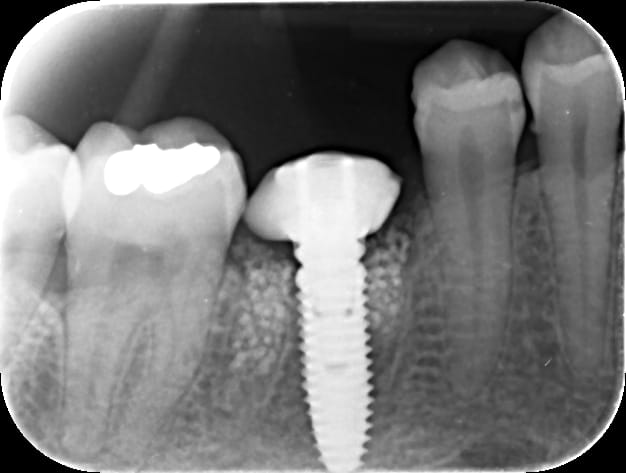

bon bein vu que vous avez été sage, une p'tite vidéo...;-)

et la radio cicat à 3 mois...

il reste des granules de kasios tcp, mais je vais faire bientôt la prothèse, l'implant est ostéointégré...